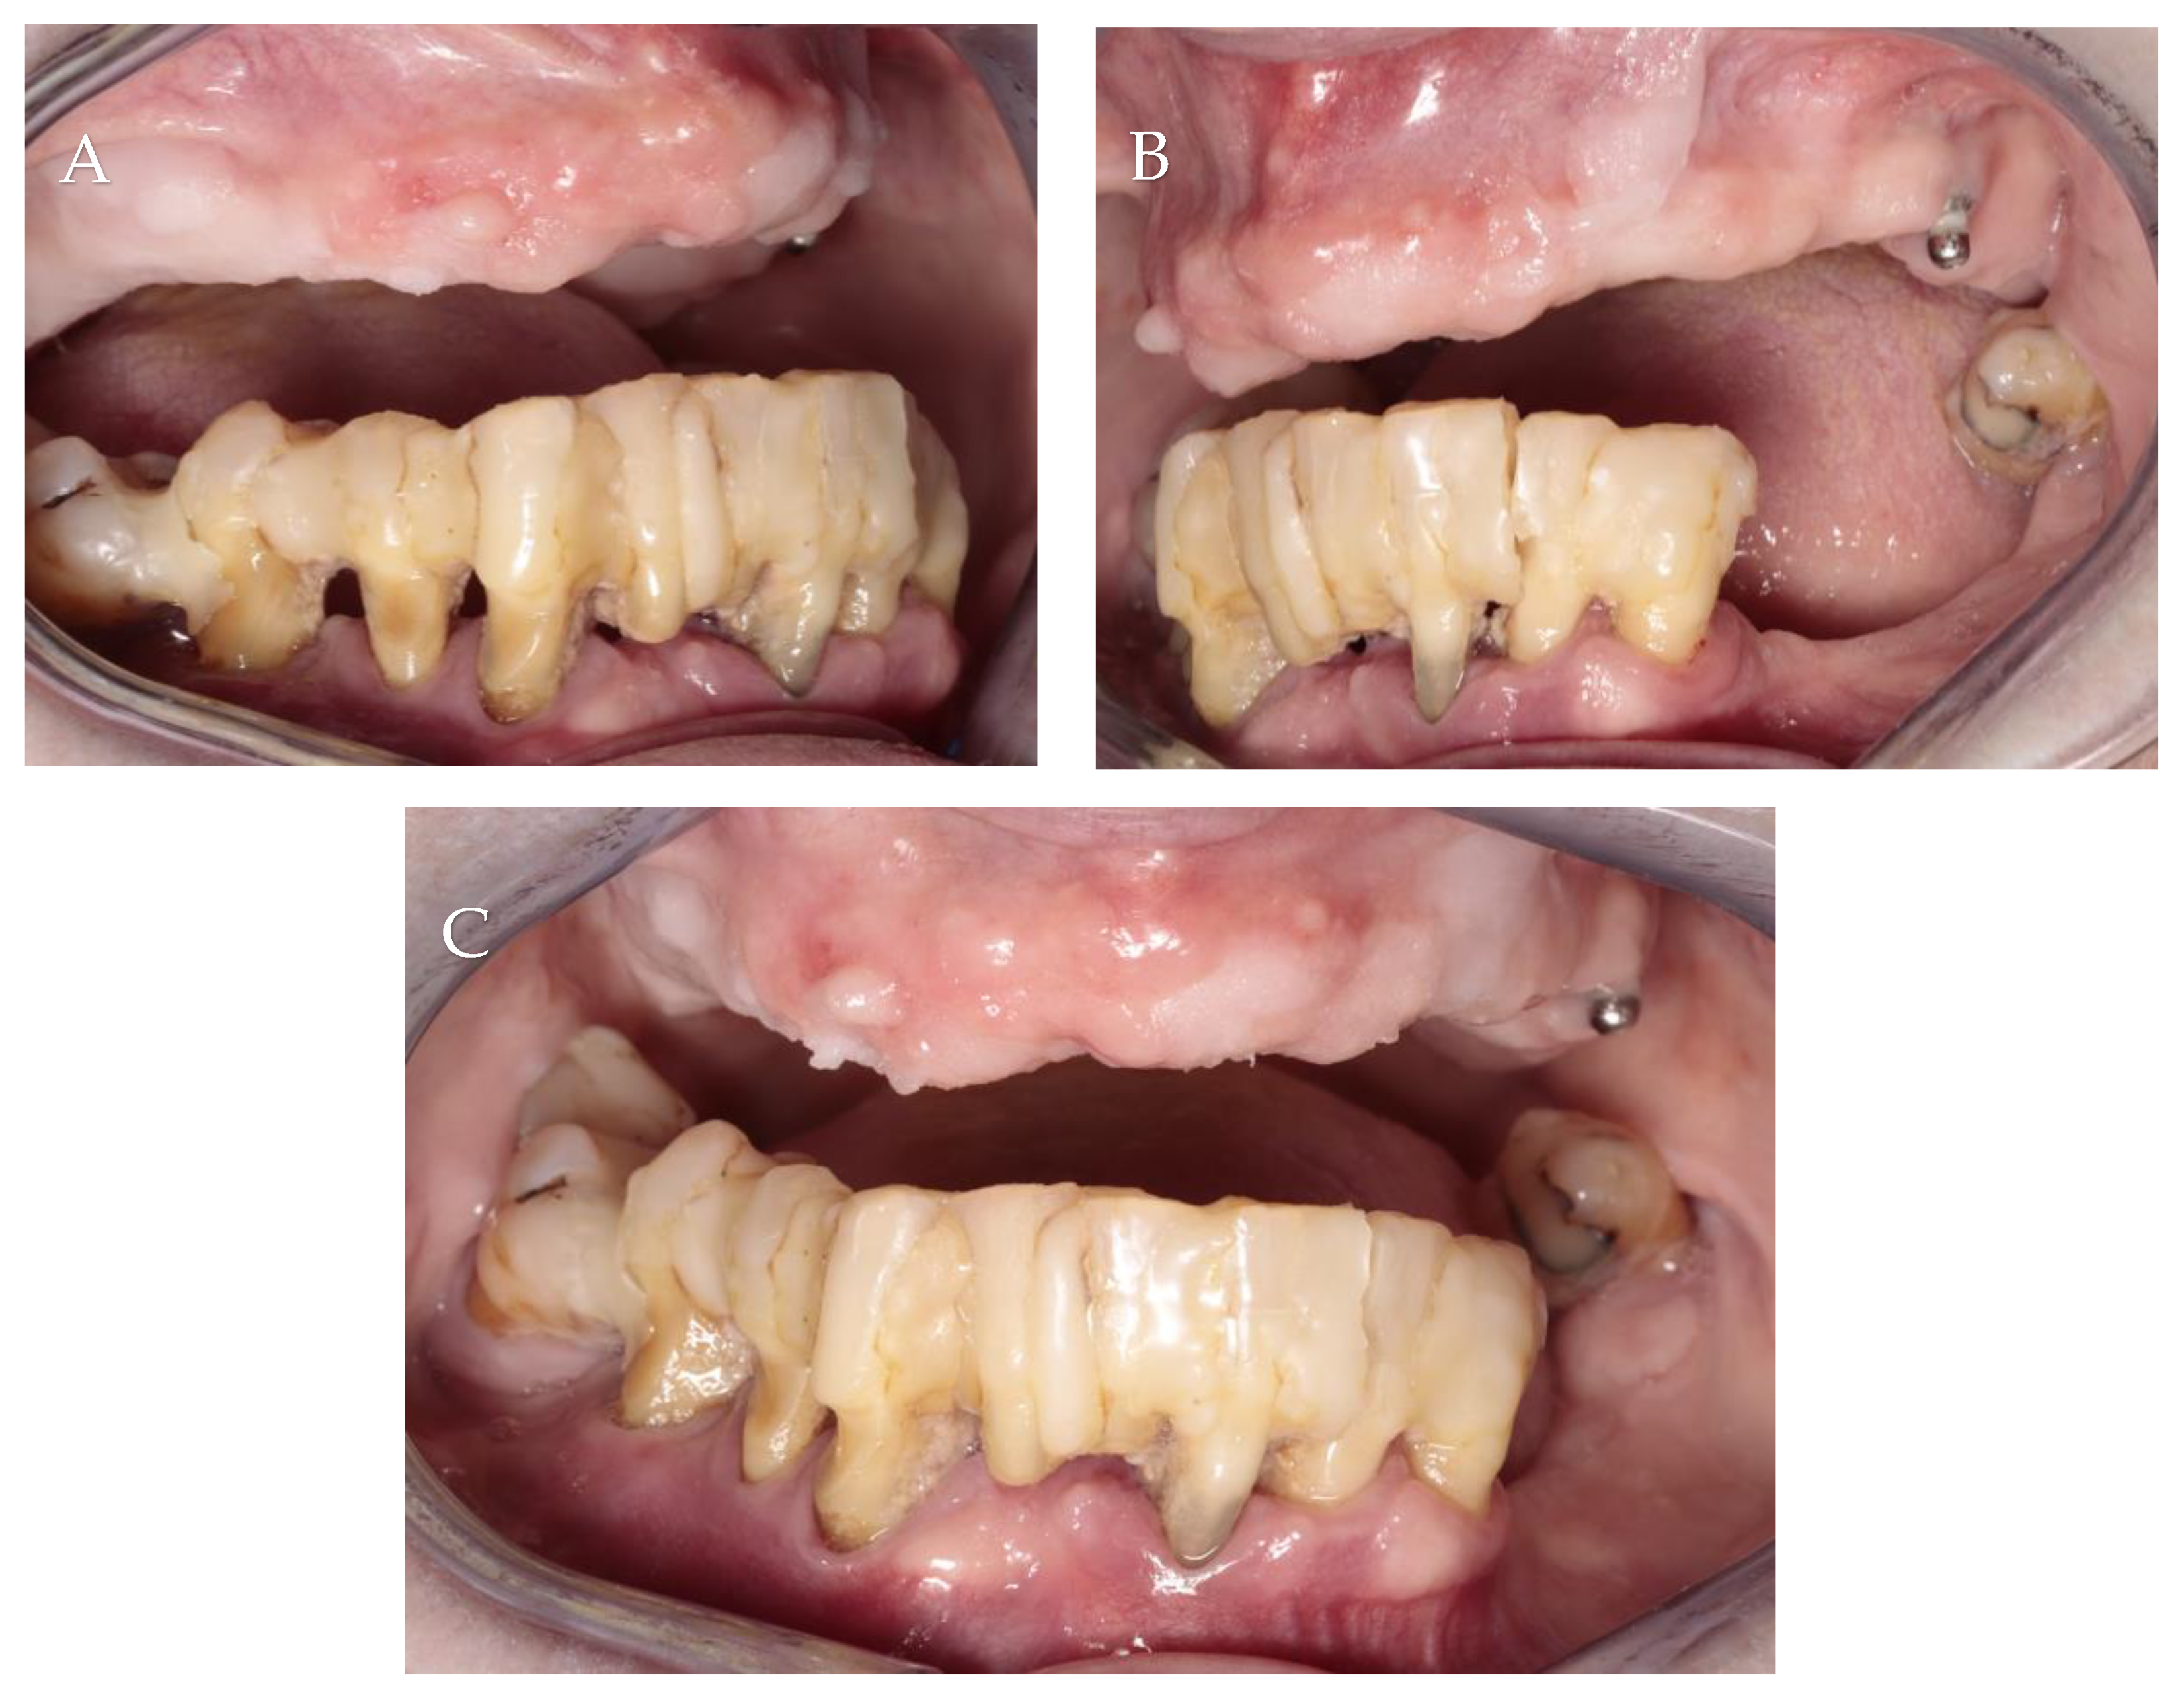

3.1. Patient Information, Diagnosis and Treatment Plan

3.2. Surgery 1—Teeth Extraction and Periodontal Lesion Enucleation with Simultaneous Implantation